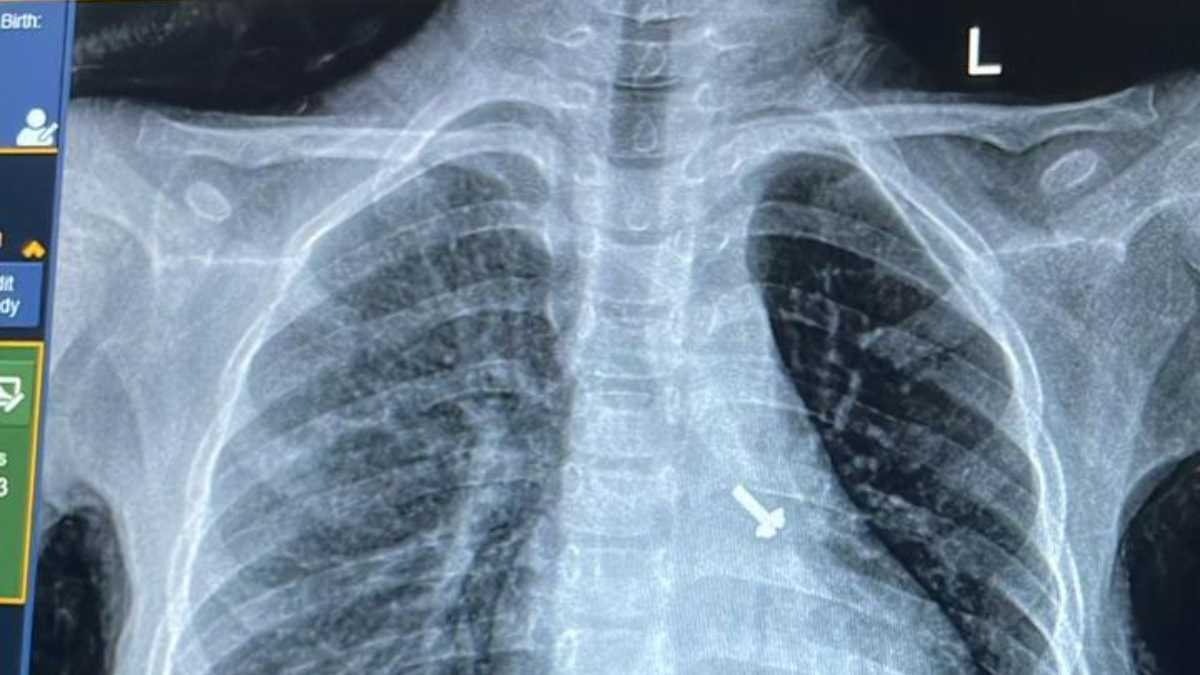

बालरोग विशेषज्ञ डॉ. व्यास कुमार राठौड़ के मुताबिक बच्चे की कुछ प्रारंभिक जांचें कराई गईं, जिसमें उसकी छाती के एक्स-रे एवं सीटी स्कैन में बच्चे के फेफड़े में एक पेंच दिखाई दिया है । इस विषय में चिकित्सक द्वारा बच्चे के अभिभावकों से पूछे जाने पर उन्हें बताया गया कि बच्चे ने घर में खेल-खेल में पेंच निगल लिया, जिसका पता परिजनों को नहीं लग पाया ।